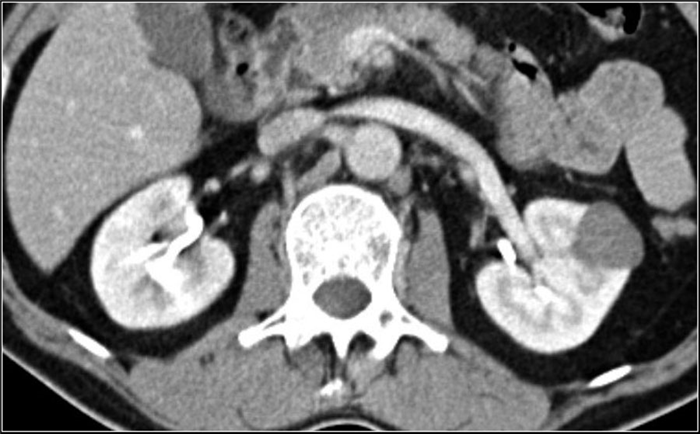

(Слева) КТ с контрастированием, аксиальная проекция: выявлена увеличенная правая почка с множественными скоплениями жидкости неправильной формы, не накапливающими контраст. Данные признаки характерны для многоочаговых абсцессов.

(Справа) КТ с контрастированием, аксиальная проекция: выявлены многокамерные абсцессы почки с ободковым контрастированием и абсцессы околопочечного пространства.